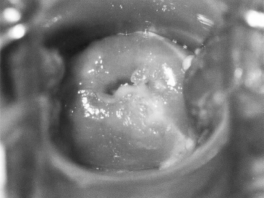

1.4.2.7.3三、临床表现

1.4.2.7.4四、诊断要点